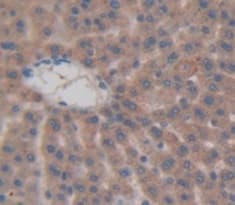

Anti-CALCB antibody(ab231662)

Rabbit Polyclonal CALCB antibody. Suitable for WB, IHC-P and reacts with Rat samples. Immunogen corresponding to Recombinant Full Length Protein corresponding to Rat Calcitonin gene-related peptide 2.

Applications IHC-P, WB

Species Reactivity Rat